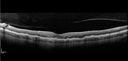

55 year old man: His mother and her siblings have been previously diagnosed with L-ORD - an autosomal dominant dystrophy resulting from a mutation in the c1qtnf5 gene on chromosome 11. The right eye has been abnormal for about the last 1.5 months. When he was trying to read street signs he noticed that his vision was not right. He then covered each eye and noticed that the left eye was normal but the right eye had an area that was blurred with a curve in lines. His right eye with initial vision of 20/32 had a CNVM on FA and responded to monthly Lucentis therapy with restoration of vision to 20/25 after monthly injections. The left eye sees 20/16

Late Onset Retinal Degeneration (L-ORD)562 views55 year old with acute vision loss from a CNVM in the right eye. He responded to Lucentis therapy. His mother and her family has been confirmed genetically to have L-ORD and were part of the early reports.00000